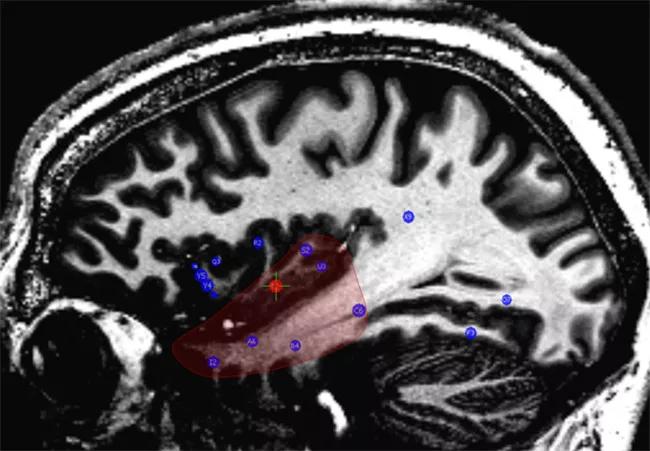

The SEEG findings led to recommendation of a resection of the right anteromesial temporal and posterior ventral insular structures (Figure 5).

Figure 5. Left: Preoperative MRI with implanted electrodes (blue) and regions that identified as epileptogenic (red). Right: Postoperative MRI showing the resection, which included the right temporal lobe and right posterior insula.